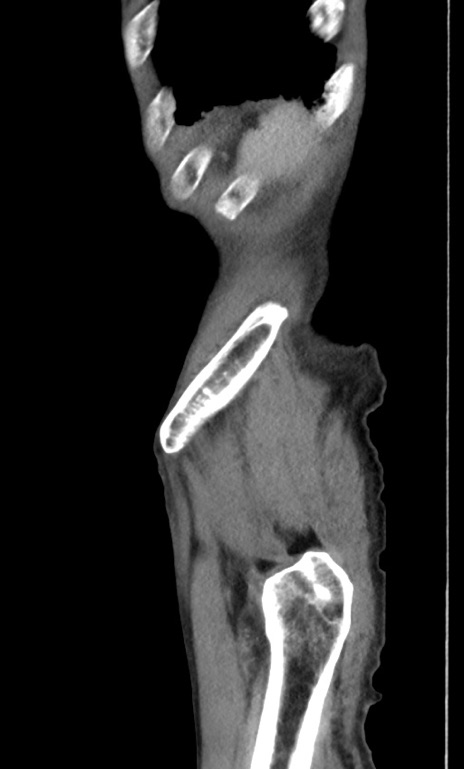

症例3(矢状断像)

【症例】 70歳代男性

【主訴】右鼠径部腫瘤、疼痛

【現病歴】本日朝より上記主訴あり、受診。

【既往歴】膀胱癌にて膀胱全摘、両側尿管皮膚瘻

【データ】WBC 5600、CRP 0.56